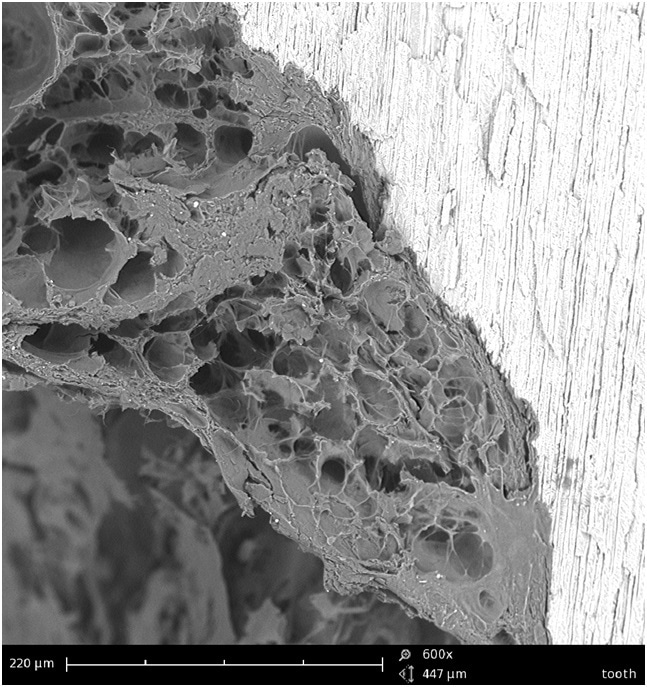

Figure 1 interface of filling ant tooth